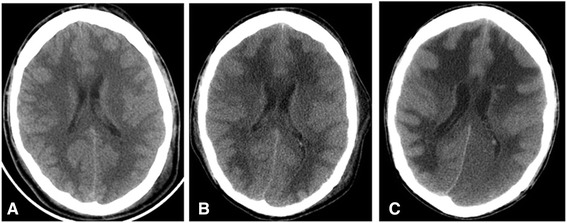

A chest X-ray done in the day of presentation showed an evidence of bilateral lung infiltrates more in the left side. A computed tomography (CT) scan of the brain without contrast done in the same day did not reveal any hemorrhage, space occupying lesion or territorial infarction. The brain parenchyma looked normal with preserved grey-white matter differentiation (Figure 1A).

In the fifth day of admission, he was found to have fixed dilated left pupil and normal reactive right one. His level of consciousness was the same. Physical examination showed generalized hypotonia with bilateral extensor plantar responses. Intravenous mannitol was given and urgent CT scan of the brain showed a clear generalized diffuse hypodensity involving the subcortical white matter (Figure 1B). MRI brain done in the 7th day of admission which showed diffuse white matter changes with sparing of the brain stem and cerebellum (Figures 2 and 3).

In the 23rd day of admission, the patient had bilaterally dilated unreactive pupils with absence of brainstem reflexes. CT scan of the brain showed increasing in the white matter hypodensity with evidence of tonsillar herniation and subsequent new left occipital infarction in the posterior cerebral artery territory. The patient was declared brain dead after fulfilling the brain death criteria.